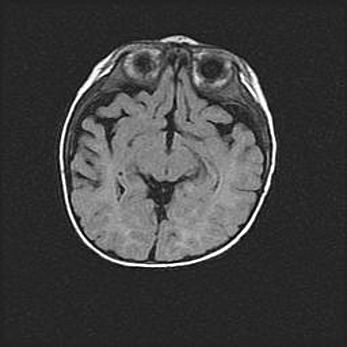

Множественные кисты обоих полушарий головного мозга, наибольшая из них в правой затылочной области. Ассиметричная атрофическая гидроцефалия.

Возраст: 7 месяцев

Вес: 5660 г

Пол: мужской

Окружность головы: 41,5 см

Срок гестации: 28-29 недель

Кисты головного мозга развиваются в результате многоочаговых некрозов вещества мозга и возникают вследствие перенесенной перинатальной инфекции, менингитов, энцефалитов, асфиксии, родовой травмы, расстройств мозгового кровообращения различного генеза. Образованию кист в веществе головного мозга плодов и новорожденных способствуют такие факторы, как высокое содержание в нем воды, недостаточная (или отсутствие) миелинизация и слабая астроглиальная реакция на повреждение.

Кисты могут сочетаться с гидроцефалией и другими поражениями головного мозга.